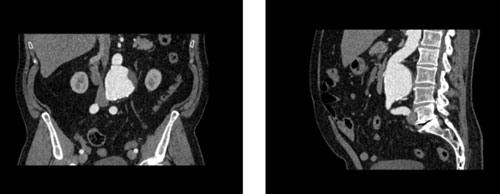

WEK53-05腹部模體,WEK53-05動脈瘤腹部模體,WEK53-05 CT血管造影模型模擬了動脈期的造影劑增強腹部。它覆蓋第一腰椎至第四骶椎。它有一個腎下腹主動脈瘤。

WEK53-05腹部模體,WEK53-05動脈瘤腹部模體成像效果圖:

SAG:

WEK53-05動脈瘤腹部模體,WEK53-05腹部模體,動脈瘤腹部模體,CT血管造影模型,WEK53-05腹部模型